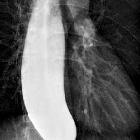

Fluoroscopy with barium swallow

A barium swallow study may be used to confirm esophageal dilatation, in addition to assessing for mucosal abnormalities.

Findings include:

- bird beak sign or rat tail sign

- esophageal dilatation

- tram track appearance: central longitudinal lucency bounded by barium on both sides

- incomplete lower esophageal sphincter relaxation that is not coordinated with esophageal contraction

- pooling or stasis of barium in the esophagus when the esophagus has become atonic or non-contractile (a late feature in the disease)

- uncoordinated, non-propulsive, tertiary contractions (see case 1)

- failure of normal peristalsis to clear the esophagus of barium when the patient is in the recumbent position, with no primary waves identified

- when the barium column is high enough (with the patient standing), the hydrostatic pressure can overcome the lower esophageal sphincter pressure, allowing passage of esophageal content